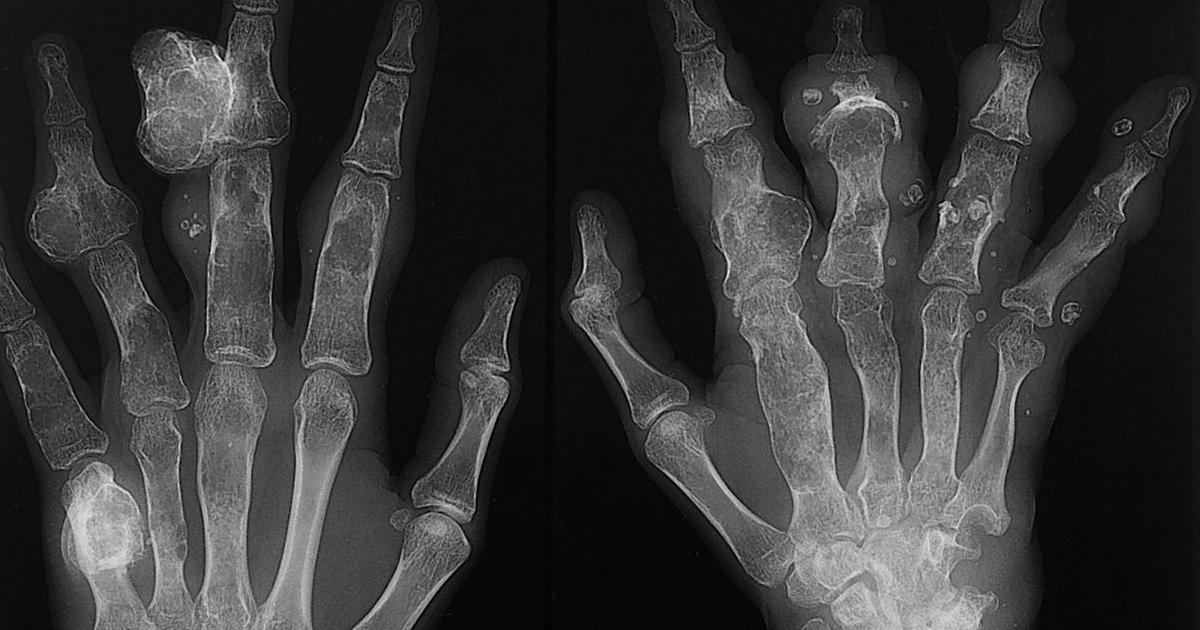

Ollier Disease

Photo Credit: Reddit

Ollier disease is a condition where multiple benign or noncancerous cartilage tumors called enchondromas develop throughout the skeletal system of the body. A spontaneous mutation in the genes causes Ollier disease to develop. This gene mutation is not one that spreads through families or is inherited. Instead, it happens randomly to an individual in utero or before they are born. The enchondromas that develop in Ollier disease patients are a result of the cartilage cells expanding in an abnormal location. This irregular growth can happen in the form of a projection from a bone, or it can occur inside of a bone. Additional DNA mutations may occur in individuals who already have the gene mutation that causes Ollier disease that accounts for the mechanism that causes enchondromas to become cancerous. When enchondromas become cancerous, they are considered chondrosarcomas. It is not uncommon for one or more of the benign tumors in individuals with Ollier disease to become malignant or cancerous over some time, so Ollier disease patients are at an increased risk for developing chondrosarcoma.